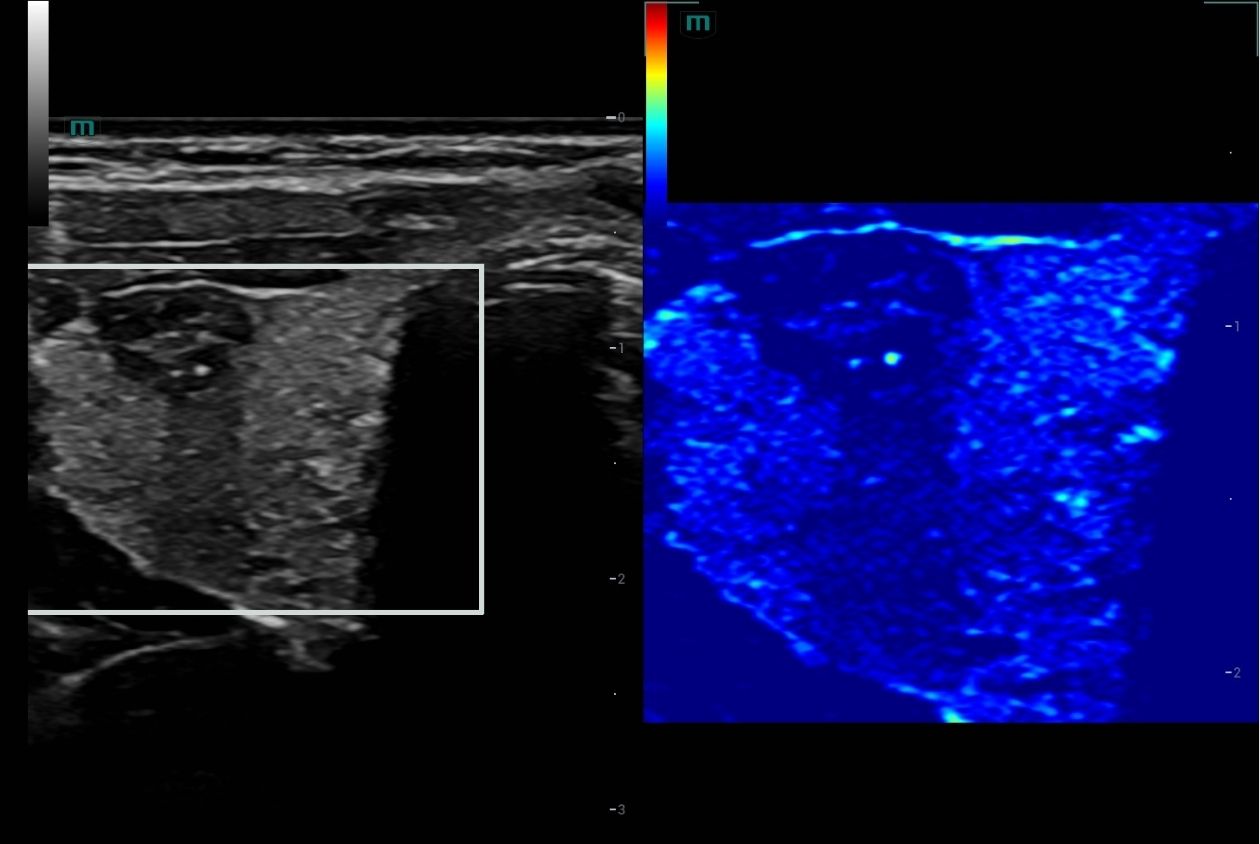

A closer look at just a few of our transducers: